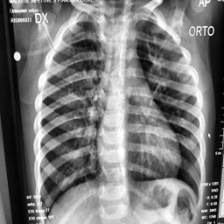

Coronavirus Disease 2019 (COVID-19) demonstrated the need for accurate and fast diagnosis methods for emergent viral diseases. Soon after the emergence of COVID-19, medical practitioners used X-ray and computed tomography (CT) images of patients' lungs to detect COVID-19. Machine learning methods are capable of improving the identification accuracy of COVID-19 in X-ray and CT images, delivering near real-time results, while alleviating the burden on medical practitioners. In this work, we demonstrate the efficacy of a support vector machine (SVM) classifier, trained with a combination of deep convolutional and handcrafted features extracted from X-ray chest scans. We use this combination of features to discriminate between healthy, common pneumonia, and COVID-19 patients. The performance of the combined feature approach is compared with a standard convolutional neural network (CNN) and the SVM trained with handcrafted features. We find that combining the features in our novel framework improves the performance of the classification task compared to the independent application of convolutional and handcrafted features. Specifically, we achieve an accuracy of 0.988 in the classification task with our combined approach compared to 0.963 and 0.983 accuracy for the handcrafted features with SVM and CNN respectively.